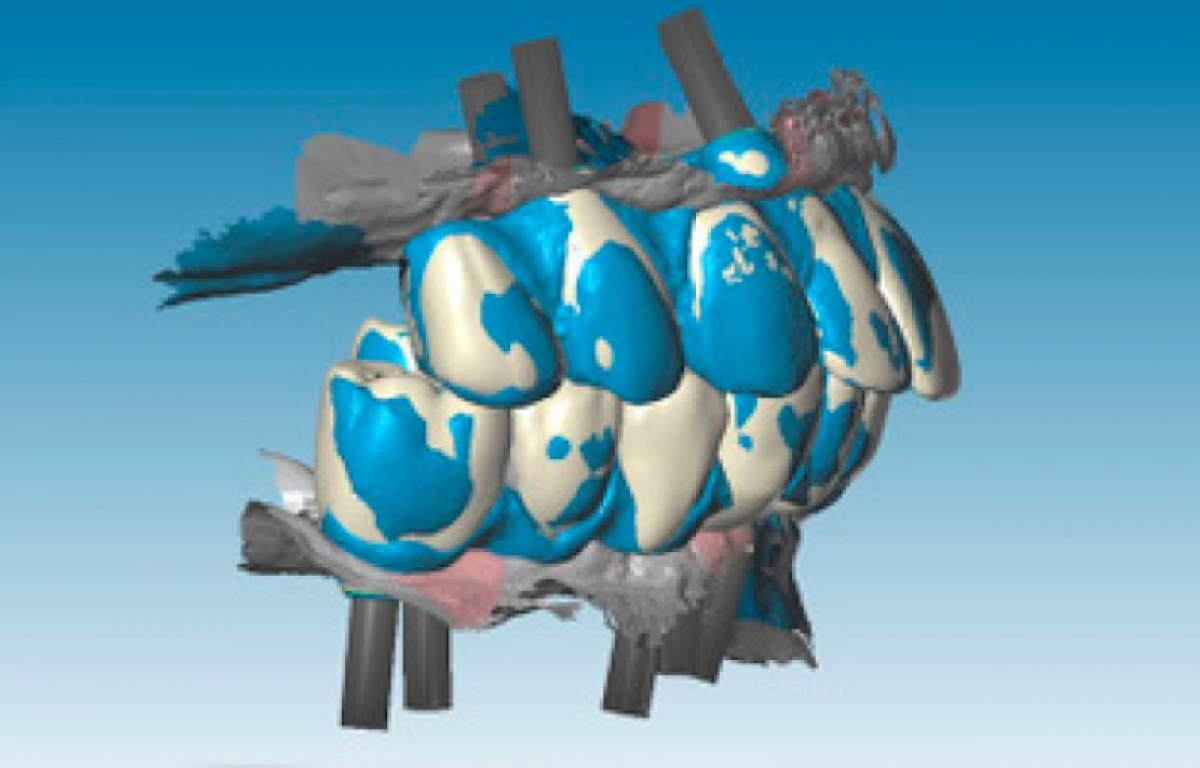

In this phase it is not possible to collect information about the occlusal relations between the two arches since there is no occlusal stop or stop. Finally, to collect the negative information about the soft tissues adjacent to the prostheses (implant emergence profile and gingival anatomy underlying the pontic elements), the upper and lower provisional were scanned outside the mouth and the third set of impressions ( STL3) was thus obtained. The three series of impressions STL1, STL2, STL3 were then imported into Geomagic Studio 12 software (3D Systems, Rock Hill, SC, USA) and combined using a specific automatic coupling algorithm. Since the gingival tissues scanned in the STL1 and STL3 series were the same, the software identified a good automatic coupling. Thereafter, the STL2 impressions were also coupled thanks to the correspondence between the form of the provisionals acquired in STL2 and STL3.Through the CAD union of the different fingerprints, a single file was obtained, called STL4, which contained the following information: three-dimensional scanbody position, soft tissue architecture, occlusal parameters and esthetic characteristics. The STL4 file was then imported into dental software (Dental Wings, Montréal, QC, Canada) to automatically and certify the position of the implants starting from the scanbodies (Figure 3).

Similarly, two resin prototypes were designed and produced to evaluate occlusal and esthetic parameters on the patient (Figures 6, 7).